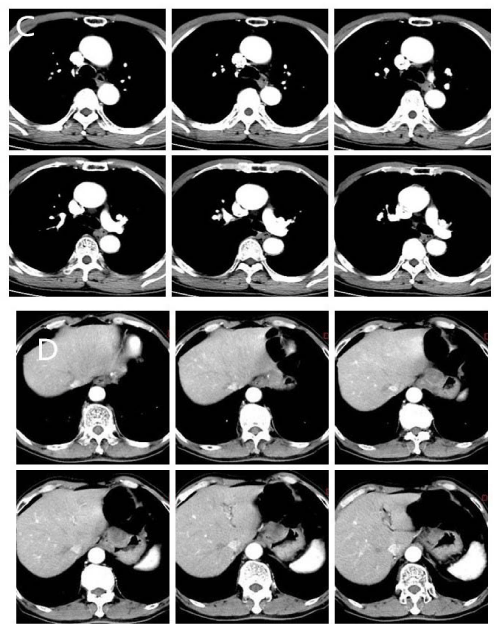

A 67-year-old man complained of intermittent upper abdominal distension. Gastroscopy showed that high-grade intraepithelial neoplasia of esophageal squamous growth 29cm from the incisors (Figure A), He underwent the ESD for the esophagus lesion (Figure B), pathologic proved that squamous cell carcinoma invaded the submucosa with a depth of more than 750 um. Computed tomogram (CT) of Chest and abdomen showed thickening of the middle esophageal wall, considering esophageal cancer, lesions between the stomach at the lower esophagus and cardia, and the possibility of stromal tumors or leiomyomas (Figure C, D). Barium meal of upper digestive tract asserted equally the rigid and filling defect of middle thoracic esophageal tube wall was observed, and no obvious niche and filling defect was found in gastric wall (Figure E). Because of the attack of cerebral infarction, the patient rejected the surgery and refuse to the chemotherapy in the followup planning. He underwent radiation therapy only for the primary esophagus. A 3D-CRT plan was designed, the planning target volume (PTV) was 60Gy in 30 fractions. After the recovery of the radiotherapy, and patients received the resection of partial gastrectomy plus small curvature lymphadenectomy. The operation showing that the tumors were located on the lesser curved side of the stomach, with a diameter of about 3cm, and there was a swollen lymph node with a diameter of about 2.5cm. Postoperative pathology showed moderately differentiated squamous cell carcinoma, local cancer tissue adjacent to the incision margin, considered as esophageal cancer proliferation, the left gastric lymph node also showed moderately differentiated squamous cell carcinoma. A follow-up study was performed 2 months after the surgery, no recurrence and metastasis was found.

Figure A: Gastroscopy findings: A slightly rough mucosa, reddish surface, irregular margin, the widest circumference was 2/3 weeks 29-34 cm away from the incisor. NBI + magnifying gastroscopy showed that the lesion was brown, IPCL was type B1, local type B2.